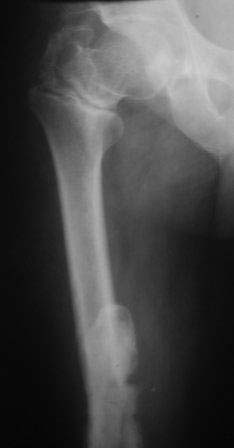

Уважаемые коллеги. Госпитализирован б-ной 47 лет, травма высотная 9 месяцев назад, тогда оперирован и/м остеосинтез ( чрезвертельный перелом не диагностирован) в одном мед.объединение, через 3 месяца почему-то штифт удален. Больной ходит с двумя костылями, ногу не нагружает, выраженная патологическая подвижность в с/з бедра, в обл вертелов патологическую подвижность определить не удается, умеренная отечность всего бедра, укорочение около 4-5см.

В плане в начале дистрактор, после устранения укорочение и репозиции БИОС реконструктивным стержнем( универсальным).